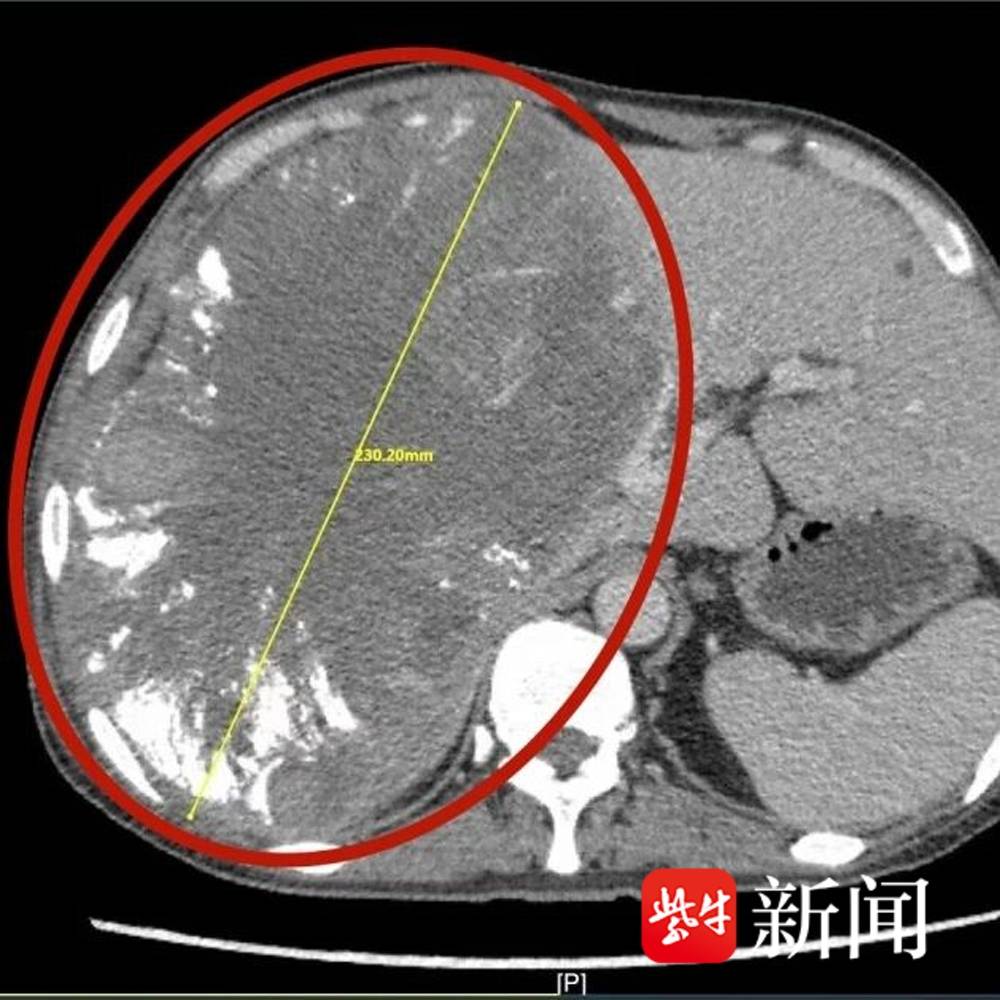

李先生此前因身体不适就医,经影像学检查发现肝脏存在巨大占位性病变,进一步诊断确诊为肝癌,肿瘤直径竟达23cm——这一尺寸远超常规肝癌手术的“安全范围”,属于典型的“巨大肝癌”。

患者肝部直径23厘米巨大肿瘤影像